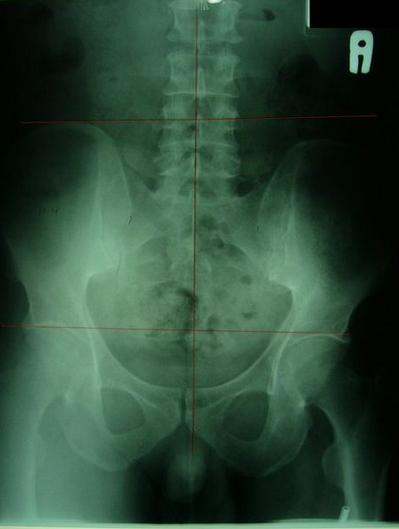

一般最常见到骨盆歪斜的案例包括产后骨盆不正、车祸、撞击、跌倒、姿势不良…等等造成。骨盆歪斜的典型症状包括腰部、髋臀部、腿、膝部疼痛。列举三个自在美国取得脊医执照以来曾经处理过骨盆歪斜相当明显的案例。都是骨盆部位曾经遭受撞击。案例A是超过十年以上的陈年车祸旧伤、另一案例B是急性摔伤(两天内)的案例。两者的X光片都依照美国脊医X摄影方式采站姿摄影评价。借此同时评价骨盆在重力(gravity)影响下的反应。也可以泯除躺歪斜摄影而造成图像不正的情况。最简单的评价要点包括骨盆高低边?中线是否穿越耻骨联合?左右两边是否对称?我简单的几条线一画,相信连外行人也可以看出明显的骨盆歪斜的情况。案例A属陈旧性伤害在调理约两个月后明显降低腰臀腿部的不舒服。而案例B属急性伤害,案例B在调理近三周后骨盆疼痛由原先的持续疼痛降低为完全不痛。之后的骨盆X光摄影重新评价也显示骨盆旋转的问题大幅改善。

案例A:右骨盆明显较低中线未穿过耻骨联合